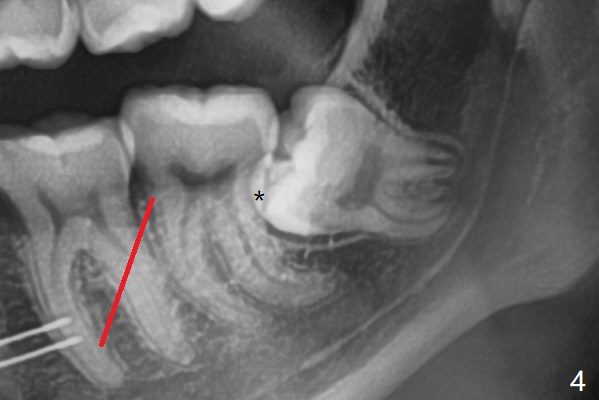

18岁女要求上大学前拔除智齿(图二),十三岁上四已经为了矫正而拔除(图一),所以现在只需要拔除下八,后者接近水平阻生,冠部可能位于下七远中颊侧(图三,四 *),所以附加切口应在七近中(红线)。智齿拔除后根部有两个牙槽窝(图五,六 *)。在右侧,塞入两个胶原塞(图七:1,2,collagen plug),其中一个末端剪开塞入根部牙槽窝。而左侧,使用一个胶原塞,但事先剪成两半(图八:1,3),第一部分也剪成燕尾,插入根部牙槽窝(1),然后在七远中放置骨水泥(1 cc Bond Apatite,2 红色),在后者上面放入胶原塞另外一半(3)。最后两侧都使用4-0 PGA 缝线。

使用胶原塞目的是预防干槽症,以前病例显示它促进骨化中心形成。骨水泥是一种医用性石膏(Biphasic Calcium Sulphate 硫酸钙 ),容易被身体吸收,3个月转换成自体骨。她哥哥(19岁)病例显示骨水泥与Osteogen Plug同样五个月会形成骨质。以后年轻人(25岁以下)智齿拔除不必植骨或者放置骨水泥。左下,右下智齿的确位于第二磨牙颊侧,事先附加切口近中,缝合后伤口不易裂开,骨粉丢失。拔除后即刻拍摄根尖片(图九,十),目的建立原有解剖,与愈合后比较,意外发现断裂牙片(F),后来取出。